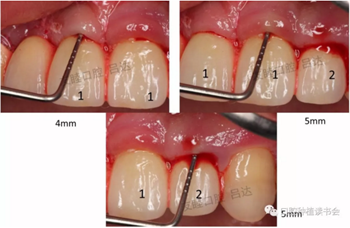

(2)口內(nèi)檢查:(圖2、3)

圖2 頰側(cè)探診深度

圖3 舌側(cè)探診深度

檢查可現(xiàn):1|12三個(gè)種植體唇側(cè)粘膜水腫,有探痛,溢膿、出血明顯,探診深度4-5mm。